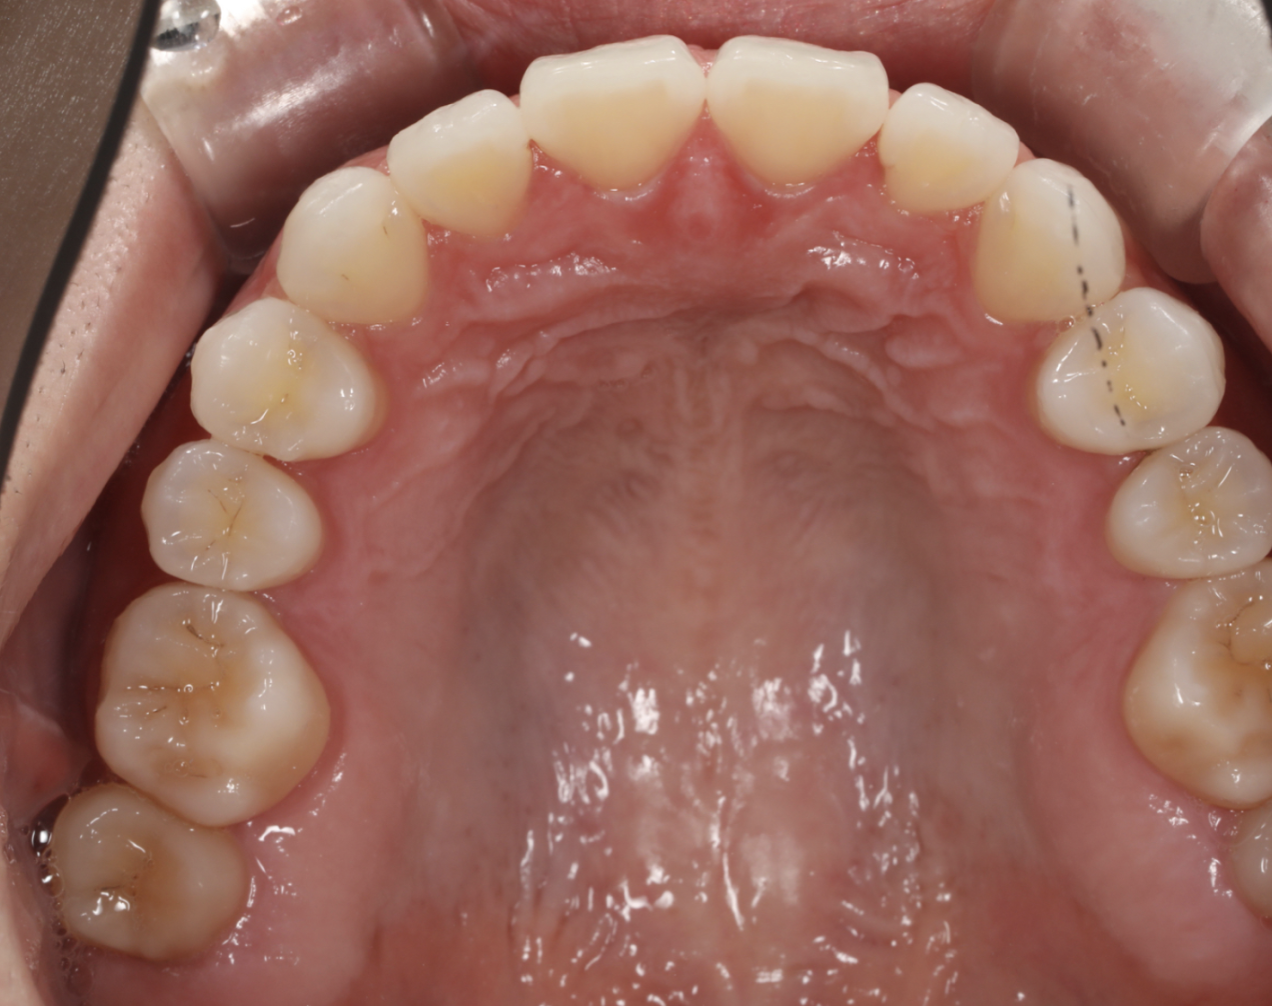

治療後の口腔写真

After

HANA Intelligence 田中千惠 すきっ歯を主訴に来院されました。費用や期間のご希望より中程度症例に対応できるインビザライン・モデレートパッケージで治療を行いました。